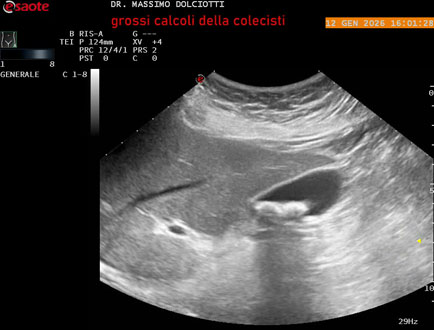

Data inserimento: 14/01/2026

Ecografia del: 12/01/2025

Strumento: Esaote MyLab Eight

Sonda: Convex Multifrequenza 1-8 MHz

Età Paziente: F 45 anni

Motivazione dell'esame: nicturia 1-2 volte.

Commento all'esame: le immagini ed il video documentano nel lume della colecisti, due immagini iperecogene, con cono d'ombra posteriore, delle dimensioni di 20,9 mm e 15,7 mm, da ricondurre a litiasi multipla.

Conclusioni: grossi calcoli della colecisti (large gallstones).

In collaborazione: Dr.ssa Marica Manfredi - Ancona, Dr. Ilir Qose - Ancona

Presentazione: Dr. Massimo Dolciotti - Ancona

Elaborazione digitale: Andrea Dini - Ancona